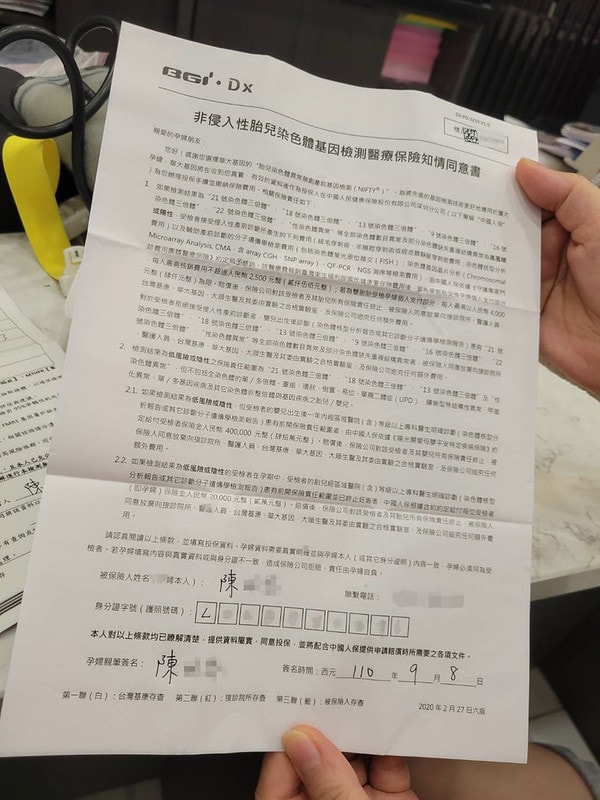

非侵入性胎兒染色體檢測

我的診所有7項、20項、94項

費用從15000~38000都有

簡單來說做越多費用就越高啦

看你們自己預算上的考量

但基本上是建議一定要做的

因為高齡產婦生出唐氏症小孩的機率比較高

因為小孩如果生出來不健康也不好

對的,我後來沒選擇做羊膜穿刺

只有做了NIPT

因為羊膜穿刺還是有千分之五的流產率

我那時候是想說因為我這家診所

如果NIPT結果不理想

要做羊穿是有幫忙申請保險的

後來我的結果都大致沒問題,就沒有選擇羊穿

但是如果有第二胎,我可能會選擇羊穿

因為羊水晶片的數據是99%準確的~

沒有說哪一個是比較好的方法

因為羊穿跟羊水晶片真的是比較準確

但是就是也是一個小手術

有的孕婦就是不想要手術

NIPT只要抽血就好了

反正兩種一定要選一種做!